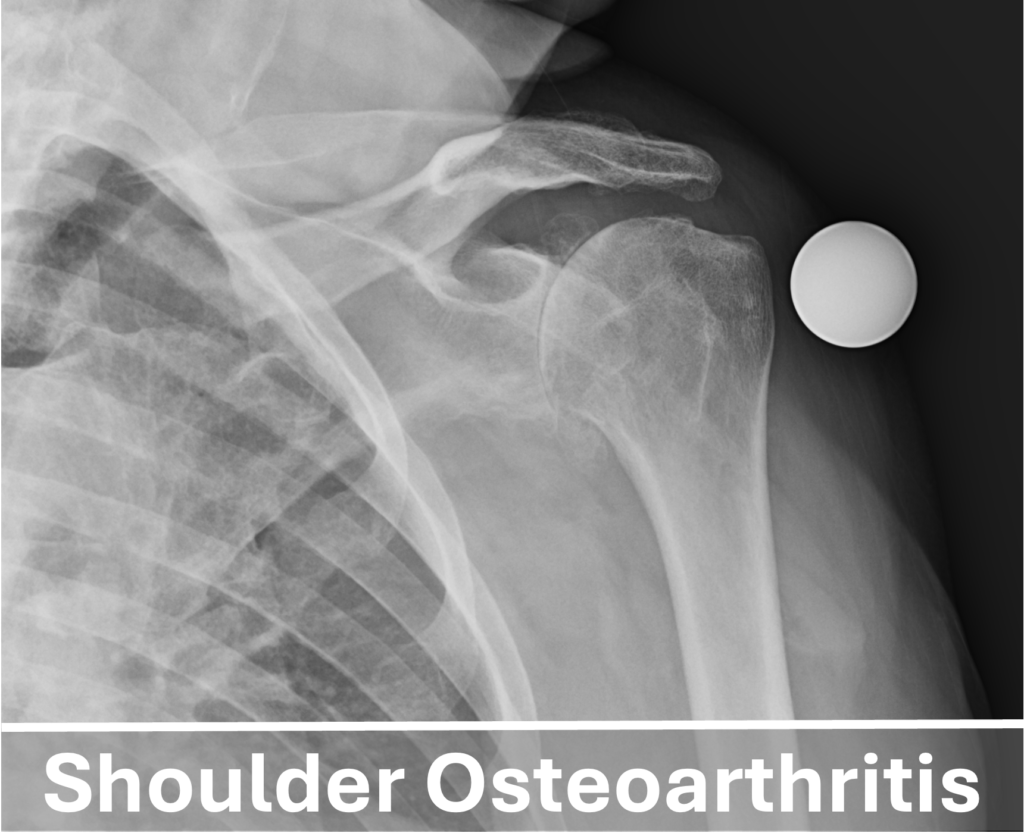

In shoulder arthritis, the cartilage of the glenoid and humeral head deteriorates, leading to inflammation that causes pain, swelling, and restricted shoulder movement. This condition is quite common, affecting nearly one in three individuals over the age of 60. The most prevalent form is shoulder osteoarthritis, which results from years of degenerative “wear and tear,” particularly in physically active individuals. Other causes include rheumatoid arthritis, a chronic autoimmune disease that targets the synovial lining of joints, and post-traumatic arthritis, which develops after injuries such as shoulder dislocations or fractures.

At the present moment, there is no “cure for shoulder arthritis. Initial treatments focus on activity modification, physical therapy, over-the-counter anti-inflammatory medications, and occasional injections to help manage symptoms and minimize the negative impact on your quality of life. When non-surgical treatments fail to provide lasting pain relief and improved function, many individuals with moderate to severe arthritis consider a shoulder replacement, also known as a shoulder arthroplasty.